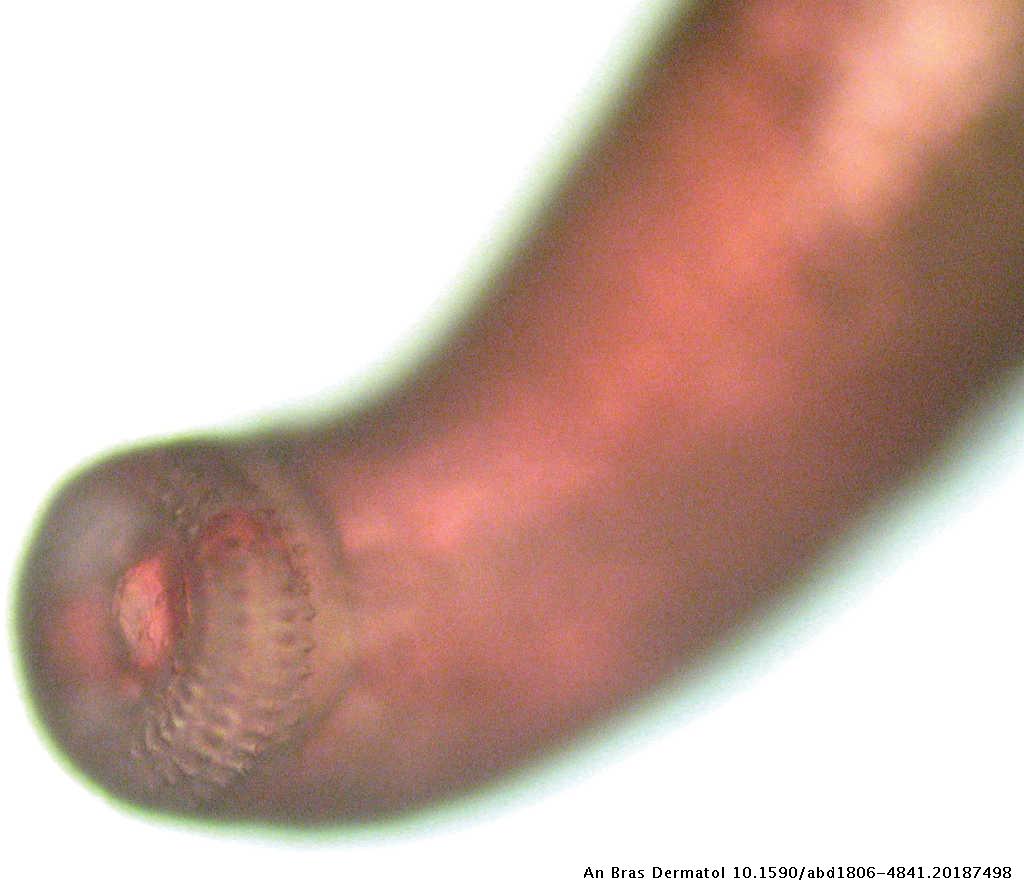

Section of a Gnathostoma sp larva in human skin biopsy sample (hematoxylin and eosin stain) Scale bar = 250 μm SYNOPSIS delineated the clinical syndromes of neurognathostomiasis, which facilitated further prospective and retrospective case identifi cation (10) With the advance of highresolution neuroimaging, the parasitic tracks of Gnathostoma could be demonstrated onHallazgo de Gnathostoma binucleatumn sp (Nematoda Spirurida) en felinos silvestres y el papel de peces dulceacuícolas y oligohalinos como vectores de la gnatostomiasis humana en la cuenca baja del Río Papaloapan, Oaxaca, Veracruz, México